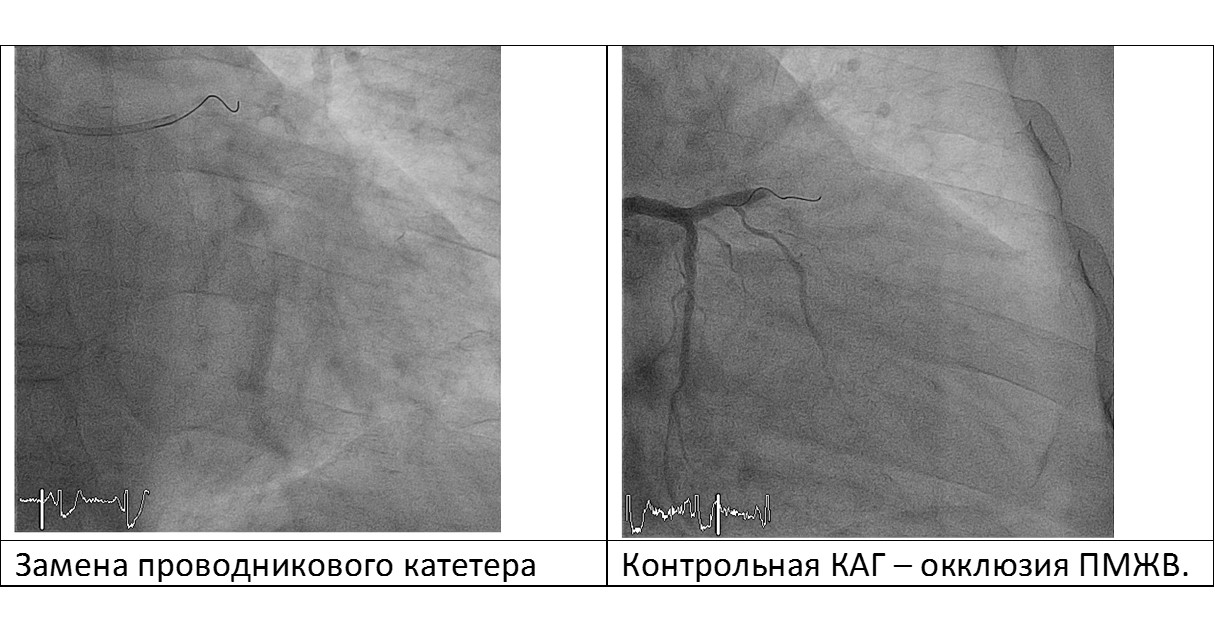

В правую бедренную артерию установлен интродьюсер 6F, проводниковый катетер CLS 4 установлен в устье ЛКА, обеспечив жесткую поддержку инструментам. При контрольной коронарографии – окклюзия ПМЖВ.

Обращает на себя внимание отсутствие хорошей поддержки проводникового катетера. В результате чего, при попытке проведения коронарного стента в зону поражения передней межжелудочковой артерии, произошла его дислокация и «потеря» проводника из истинного просвета ПМЖВ. Пациент тотчас же почувствовал сильный болевой приступ за грудиной, на ЭКГ мониторе - элевация сегментов ST. Неоднократные попытки катетеризировать ЛКА гайдом с большим «коленом» успехом не увенчались.